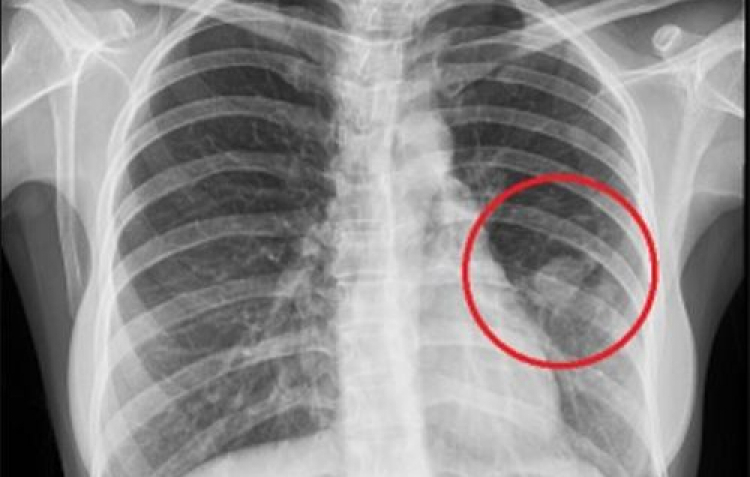

PNO - Chuyên gia Bệnh viện Bạch Mai chỉ dấu hiệu mà gần 70% người bệnh mắc phải đều được chẩn đoán mắc ung thư phổi, căn bệnh có tỉ lệ tử vong cao.